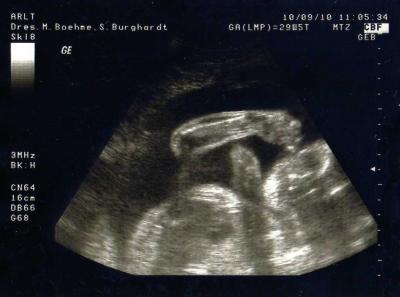

.. ich melde mich ma für Heute zurück... Hatte Heute 3tes Screening... Dem kleinen Geht es sehr sehr gut.. Ärztin staund das er sich so schön immer wieder zeigt.. Hat wieder fleißig am Daumen Genuckelt... Habe ganz schön zu genommen von 67 kg auf 74 kg Herz auch alles top... Hier ein Bild von unserer Nuckelbacke... Lg Steffi & Tylor

Bild zu Sooo.... - Forum für November - Mamis